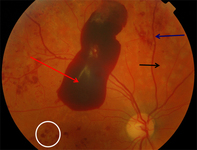

Proliferative diabetic retinopathy: macular laser burns (black arrow), misty vitreous haemorrhage (blue arrow), clot within vitreous haemorrhage (red arrow)

Courtesy of Moorfields Photographic Archive; used with permission